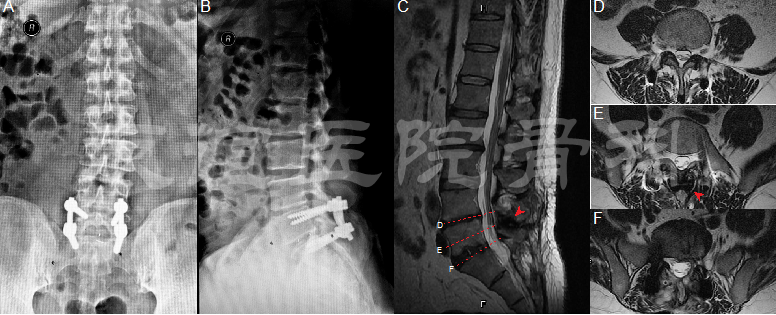

图1:术前影像学资料:腰椎正侧位片(A,B)提示:L4-5,L5-S1椎间隙明显变窄

术前CT(C)提示:L5-S1左侧椎间盘突出伴骨化

术前MRI(D-F)提示:L5-S1(F)左侧腰椎间盘突出压迫硬膜囊及左侧神经根,L4-5(E)左侧椎间盘突出。(红色箭头标记腰椎间盘突出)